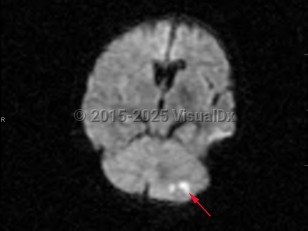

Imaging Studies image of Cerebellar stroke - imageId=7903644. Click to open in gallery.  caption: '<span>Diffusion weighted imaging  demonstrates increased signal in the left cerebellum. There was a  corresponding decrease in the ADC map, consistent with acute left  cerebellar infarction.</span>'

Diffusion weighted imaging demonstrates increased signal in the left cerebellum. There was a corresponding decrease in the ADC map, consistent with acute left cerebellar infarction.